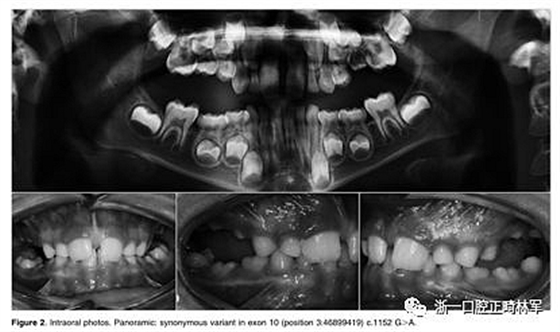

在另一个同胞(II:3)中,鉴定出在蛋白质氨基酸序列水平不引起变异的外显子,c.1152GA(rs200475872;图1A,B)中的同义变体,但涉及改变含氮碱。基于计算机分析,这种改变可能会影响mRNA的折叠并影响其半衰期和蛋白质生产。在这个患者样本中,在一个孤立的病例中发现了同样的同义变体c.1152G.A,由于PFE而具有严重的开合(图2)。

图2.口内照片。全景:外显子10中的同义变体(位置3:46899419)c.1152 G>A.

本研究中确定的低咬合的临床特征与PFE基于基因诊断和萌出障碍诊断标准的应用相一致。对特定相关牙科特征的仔细临床检查包括以下内容:至少一颗牙包括低咬合,局限于后部区域,单侧(38%;图1A)和双侧呈现(35%;图1B和2),至少有一个暂时性后牙(48%暂时;图1A,B和3A; 55%永久性,图3B)。

此外,观察到牙面特征如下:由于受影响侧的侧向开放咬伤的严重程度而引起的垂直骨骼不对称(35%;图1A,B和图3A,B);由下颌骨侧向偏离组成的面部不对称(图1A,B和图2;表4)。

这种不对称在单侧开合患者中更为明显。进一步发现受影响的患者与先前报道的患者存在上颌骨收缩和III类牙齿/骨骼关系(28%;图1A,B和图2)。至少有一例患者出现了相对于9名患者的低咬合。表4总结了PTH1R的表型结果和相关的突变分析(N = 8)。